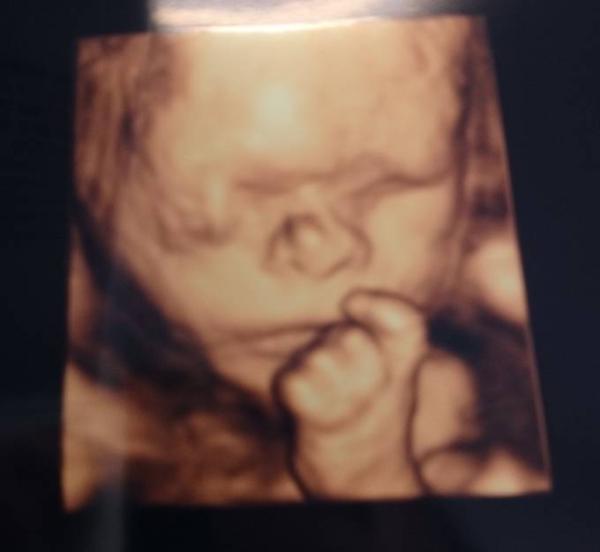

Nachdem zum zweiten Screening der Magen nicht so recht gefüllt war, war ich heute bei der feindiagnostik. Dem kleinen Mann geht's prima, alles da, alles dran, alles drin... Ich habe ein wunderschönes Bild bekommen und während die Ärztin geschrieben hat, hab ich die ersten Bewegungen von außen gesehen. Also ein gelungener Tag...

Bild zu Heute Feindiagnostik - Forum für April - Mamis

Wow was für ein mega schönes Bild und super das alles gut ist . Warum habt ihr alle Feindiagnostik? Müsst ihr das selbst bezahlen? Hatte das in der ersten ss nicht, und diesmal hat er bis jetzt auch nichts gesagt

Na herzlichen glückwunsch, dass sich alles geklärt hat und gut ist Bei dem mäusel hats wohl unter der nase gejuckt was, wie süß Also die feindiagnostik bekommt man auf krankenkasse wenn irgendwelche auffälligkeiten sind oder der gyn von eventuellen komplikationen ausgeht.. ansonsten muss man es selbst zahlen

Sehr schön und super süßes Bild